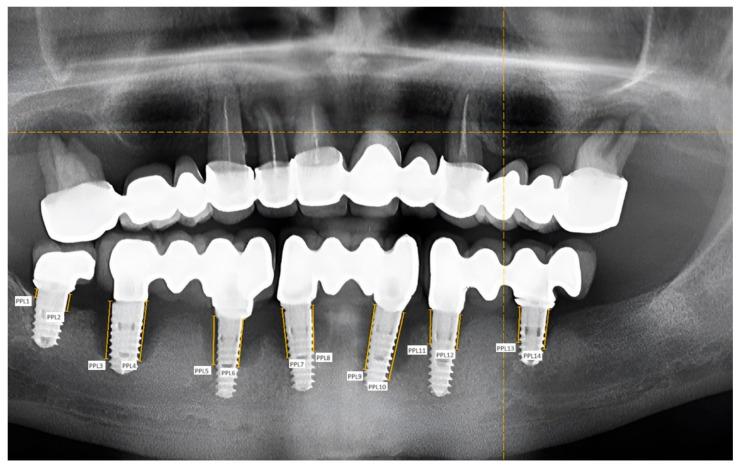

We followed 40 patients, with a total number of 92 dental implants, divided into three age groups: under 35 years, between 35 and 55 years, and older than 55 years. Patients were also divided into groups according to the time since implant placement: 1-3 years, 4-7 years, and more than 7 years. The patients were examined, and periodontal pocket depth, peri-implant pocket depth, Löe-Silness gingival index, mucosal thickness, and keratinized mucosal width were recorded; bone resorption was measured on radiographs using a 2D image analysis method; and a questionnaire was also conducted.

我们跟踪了40例患者,共92颗牙种植体,分为三个年龄组:35岁以下、35至55岁、55岁以上。患者还根据种植体植入后的时间分组:1至3年、4至7年、7年以上。对患者进行检查,记录牙周袋深度、种植体周围袋深度、洛 - 西伦牙龈指数、黏膜厚度和角化黏膜宽度;使用二维图像分析方法在X线片上测量骨吸收情况;并进行问卷调查。